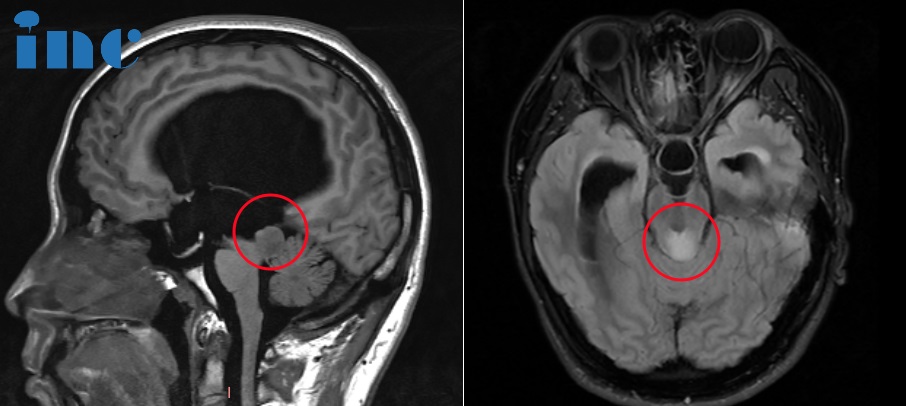

图片术前MRI影像

图片术后MRI影像